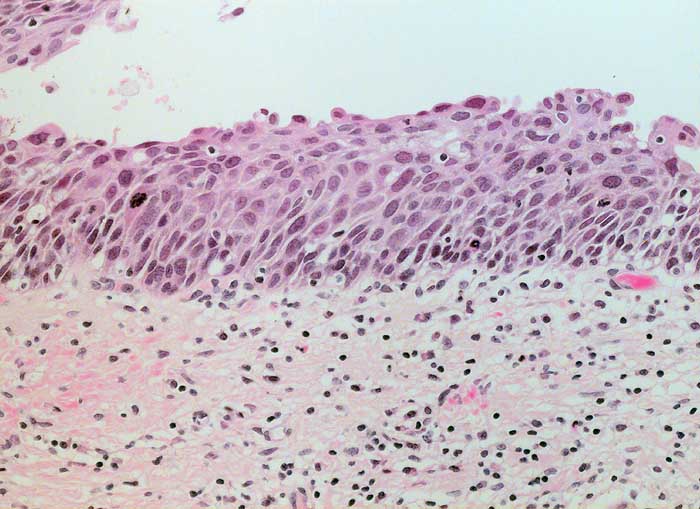

HSIL: schwere Dysplasie des Plattenepithels

Die am wenigsten differenzierten Zellen der schweren Dysplasie entsprechen dem Basalzelltyp. Die Kerne sind grösser als bei der mässigen Dysplasie. Da die Zellen gleichzeitig kleiner sind, erhöht sich die Kern-Zytoplasma Relation deutlich zu Gunsten der Kerne. Die vergrösserten Chromatingranula sind durch bandförmige Chromatinverklumpungen miteinander verbunden. Dadurch entsteht ein typisches Siebmuster. Die Kernmembran ist unregelmässig verdickt und zeigt häufig auch tiefere Einkerbungen.

Die zytologischen Bilder stammen von zwei verschiedenen Patientinnen.